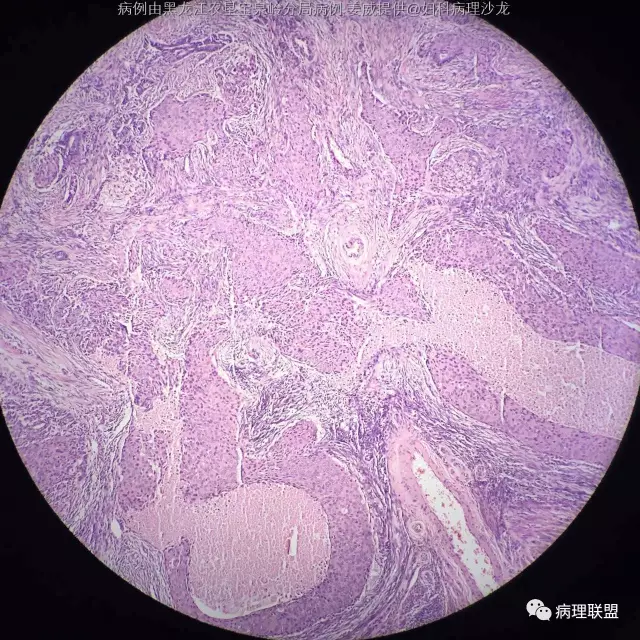

女 45岁,子宫内膜 全切子宫 术前非典(病例由黑龙江农垦宝泉岭分局病理 姜威提供,致谢!)

@黑龙江农垦宝泉岭分局病理 姜威 :子宫内膜样癌伴鳞状分化